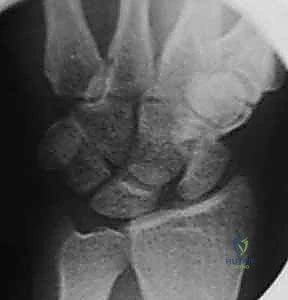

- Static Instability Signs (PA view):

- Increased Scapholunate Gap: A normal interval is less than 3 mm. Greater than 3 mm is the classic Terry Thomas sign.

- Scaphoid Ring Sign: The scaphoid collapses into flexion, causing its tuberosity to project in the coronal plane, appearing as a "ring."

- Volar Lip Overlap: The volar lip of the extended lunate may overlap with the capitate.

FIG 2 • A. PA radiograph demonstrating an increased scapholunate gap and a scaphoid ring sign. B. A fluoroscopic image of another example of an increased scapholunate gap. C. The contralateral wrist demonstrates a normal scapholunate interval.